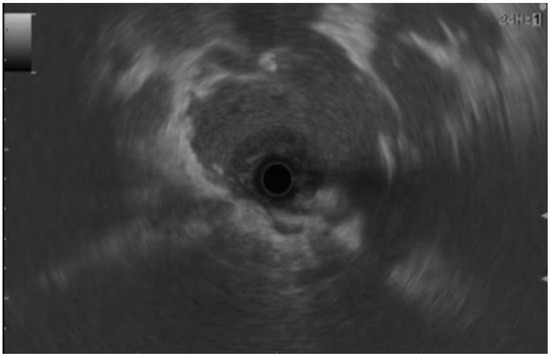

- Ishikawa, T.; Kawashima, H.; Ohno, E.; Mizutani, Y.; Fujishiro, M. Imaging Diagnosis of Autoimmune Pancreatitis Using Endoscopic Ultrasonography. J. Med. Ultrason. 2021, 48, 543–553. [Google Scholar] [CrossRef]

- Catalano, M.F.; Sahai, A.; Levy, M.; Romagnuolo, J.; Wiersema, M.; Brugge, W.; Freeman, M.; Yamao, K.; Canto, M.; Hernandez, L.V. EUS-Based Criteria for the Diagnosis of Chronic Pancreatitis: The Rosemont Classification. Gastrointest. Endosc. 2009, 69, 1251–1261. [Google Scholar] [CrossRef] [PubMed]